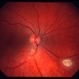

- tuberous sclerosis

- Mulberry lesion.